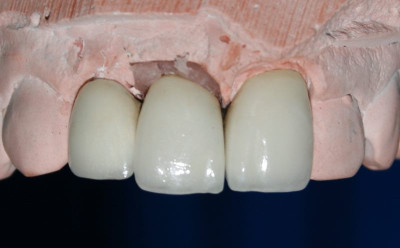

Se prepara para toma de impresión (modelo)

Trabajo de laboratorio dental